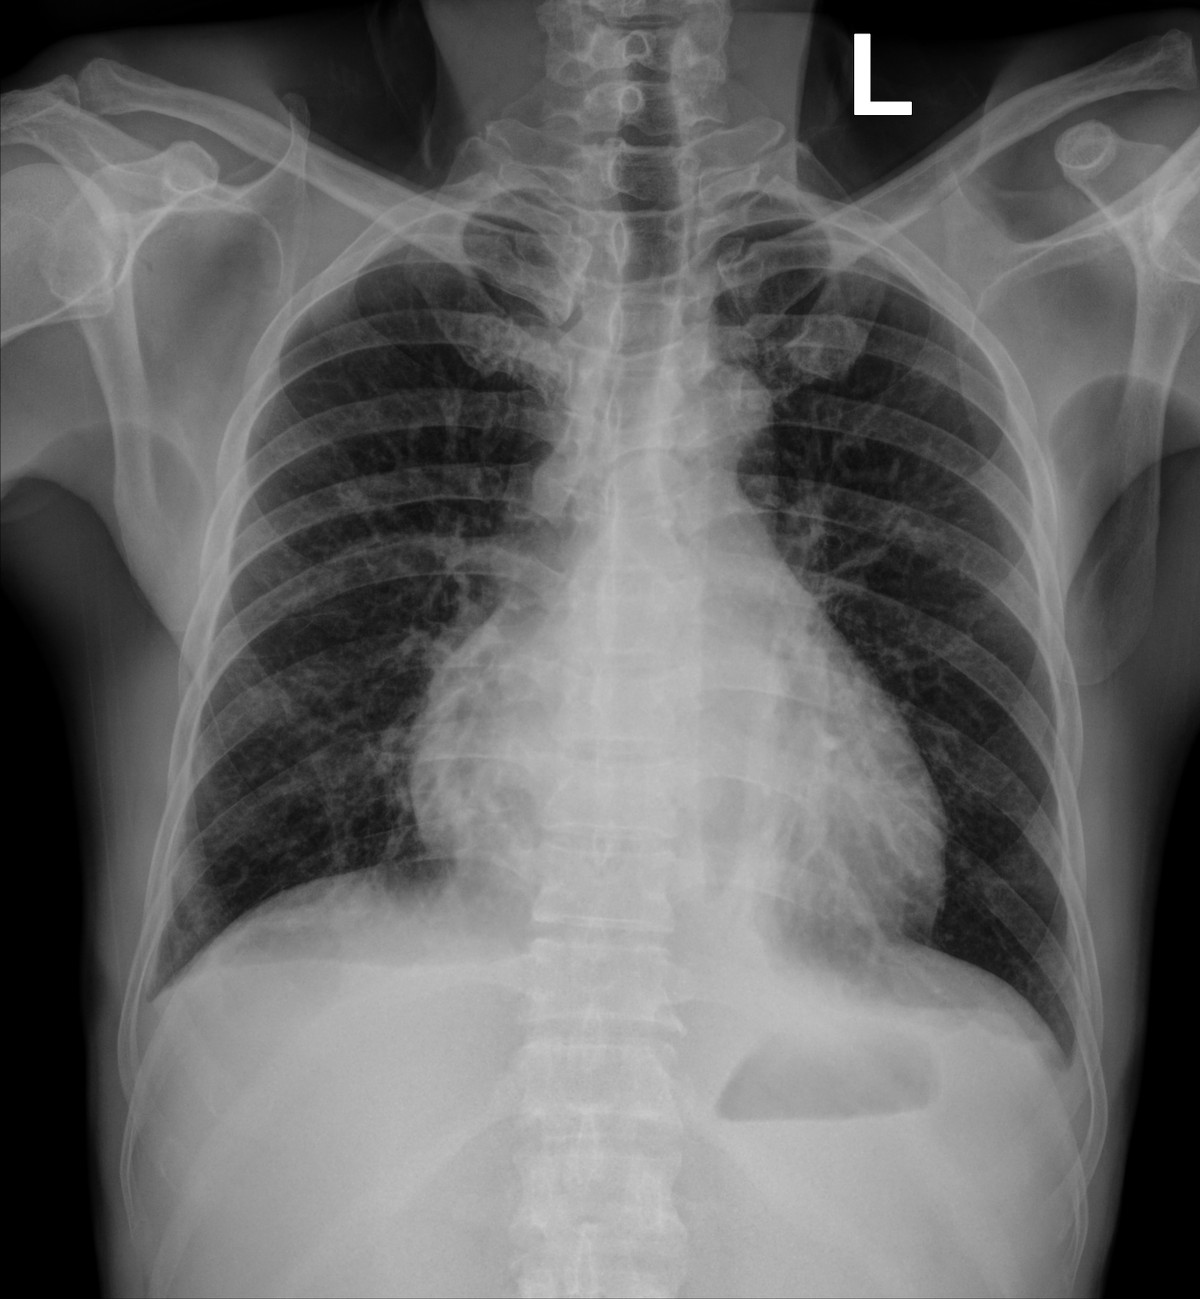

Phim chụp Xquang phổi của bệnh nhân C.Đ.C (24/10) - Ảnh BVCC

Đến ngày 24/10, trong một lần truyền huyết tương tiếp theo để xử lý tình trạng đông máu, người bệnh xuất hiện khó thở tăng dần chỉ sau khoảng 15-20 phút truyền, SpO₂ từ 97% còn khoảng 88-90%, huyết áp tăng, tĩnh mạch cổ nổi, nghe phổi có ran ẩm hai bên.

Chụp CT scan phổi thấy hình ảnh phù phổi cấp, các xét nghiệm khác phù hợp với chẩn đoán Quá tải tuần hoàn liên quan tới truyền máu (TACO). Kíp trực đã dừng truyền, cho thở oxy, đặt tư thế ngồi và dùng thuốc lợi tiểu, nên người bệnh cải thiện triệu chứng.